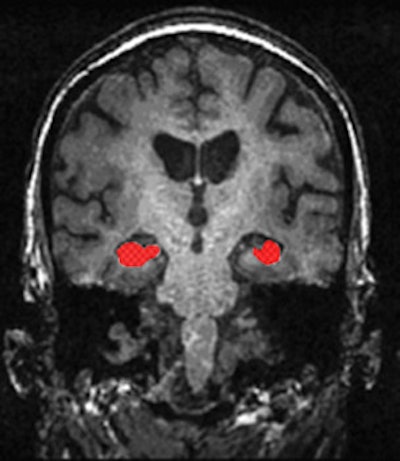

The studies in Rotterdam and similar studies elsewhere have revealed a myriad of results, he added. Notably, that size of the hippocampus is associated with development of Alzheimer's; subjects with smaller or accelerated atrophy rate of the hippocampus are more prone to develop cognitive impairment and Alzheimer's disease.

"We have also found common mutations in the gene sequence of humans that are associated with imaging phenotypes like the volume of the hippocampus. As and when some of these imaging biomarkers, in this case the size of the hippocampus, are validated through large studies, they could become screening tools," he said.